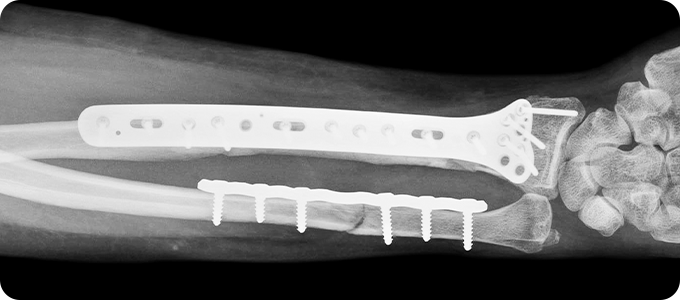

상완골 골절 수술

X-ray 및 CT를 통해 골절 형태와 전위 정도를 확인합니다.

골절된 뼈를 원래 위치로 맞추는 정복 작업을 진행합니다.

금속판, 나사, 고정막을 이용해 뼈를 고정합니다.